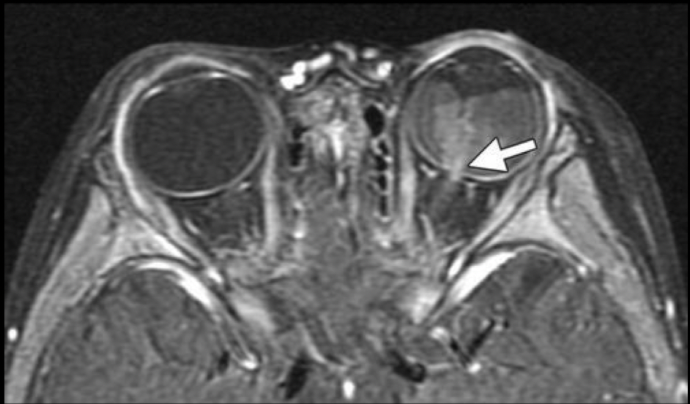

¿Qué características esperas encontrar en una RM en secuencia T1 en la enfermedad de orbitopatía tiroidea?

Agrandamiento de músculos extraoculares

¿Qué características esperas encontrar en una RM en secuencia T2 en la enfermedad de orbitopatía tiroidea?

• Aumento de señal en músculos extraoculares en fase agudas

• Diámetro disminuido del nervio óptico

¿qué enfermedad sospechas?

Orbitopatía tiroidea